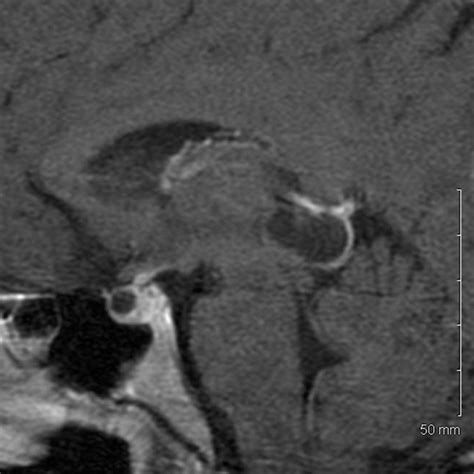

Diagnosing and Monitoring

In most instances, a Pineal Gland Cyst is discovered incidentally. Once identified, neuroradiologists evaluate the cyst using magnetic resonance imaging (MRI). The imaging helps determine the size, appearance, and whether the cyst is putting pressure on critical brain structures.

Appearance Smooth, thin-walled, and fluid-filled.